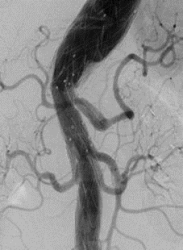

Komplexes Aneurysma der Bauchschlagader: mit einer über die Leistenregion minimal invasiv eingebrachten Stentgraft – Prothese versorgt, zusätzliche Schienung lebenswichtiger Organarterien (Nieren, Darm, Leber etc.) – sog. 4-fach gebranchte Prothese

Dabei handelt es sich zumeist um modulare Prothesensysteme. Hierdurch wird der Gefäßstrom durch die Prothese geleitet und somit das Aneurysma ausgeschaltet.

Minimalinvasive Eingriffe haben den Vorteil einer erniedrigten peri/postoperativen Mortalität, einer deutlich verkürzten Liegedauer und benötigen so gut wie keine rehabilitierenden Maßnahmen, allerdings müssen die Aortenprothesen jährlich mittels CT-Angiographie kontrolliert werden um etwaige Komplikationen (weiteres Aneurysmawachstum, Materialdefekte) frühzeitig zu erkennen und in weiterer Folge auch beheben zu können.